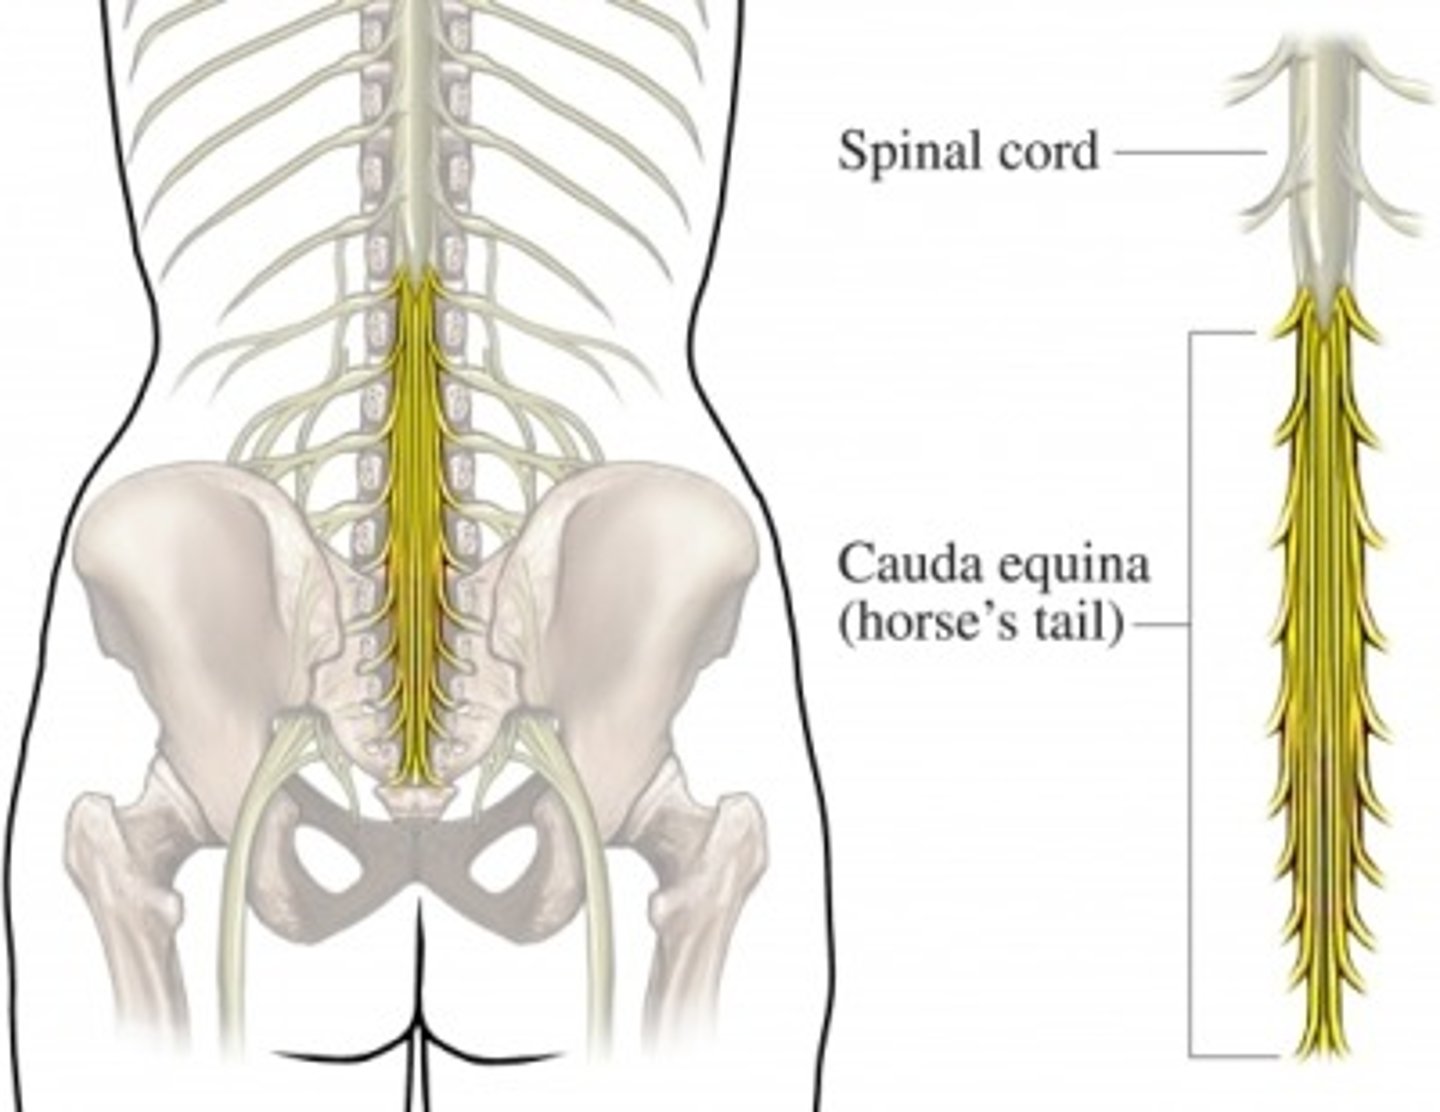

cauda equina

Nerve roots from spinal cord to lower intervertebral foramen to exit

L2 to S5 and filum terminale